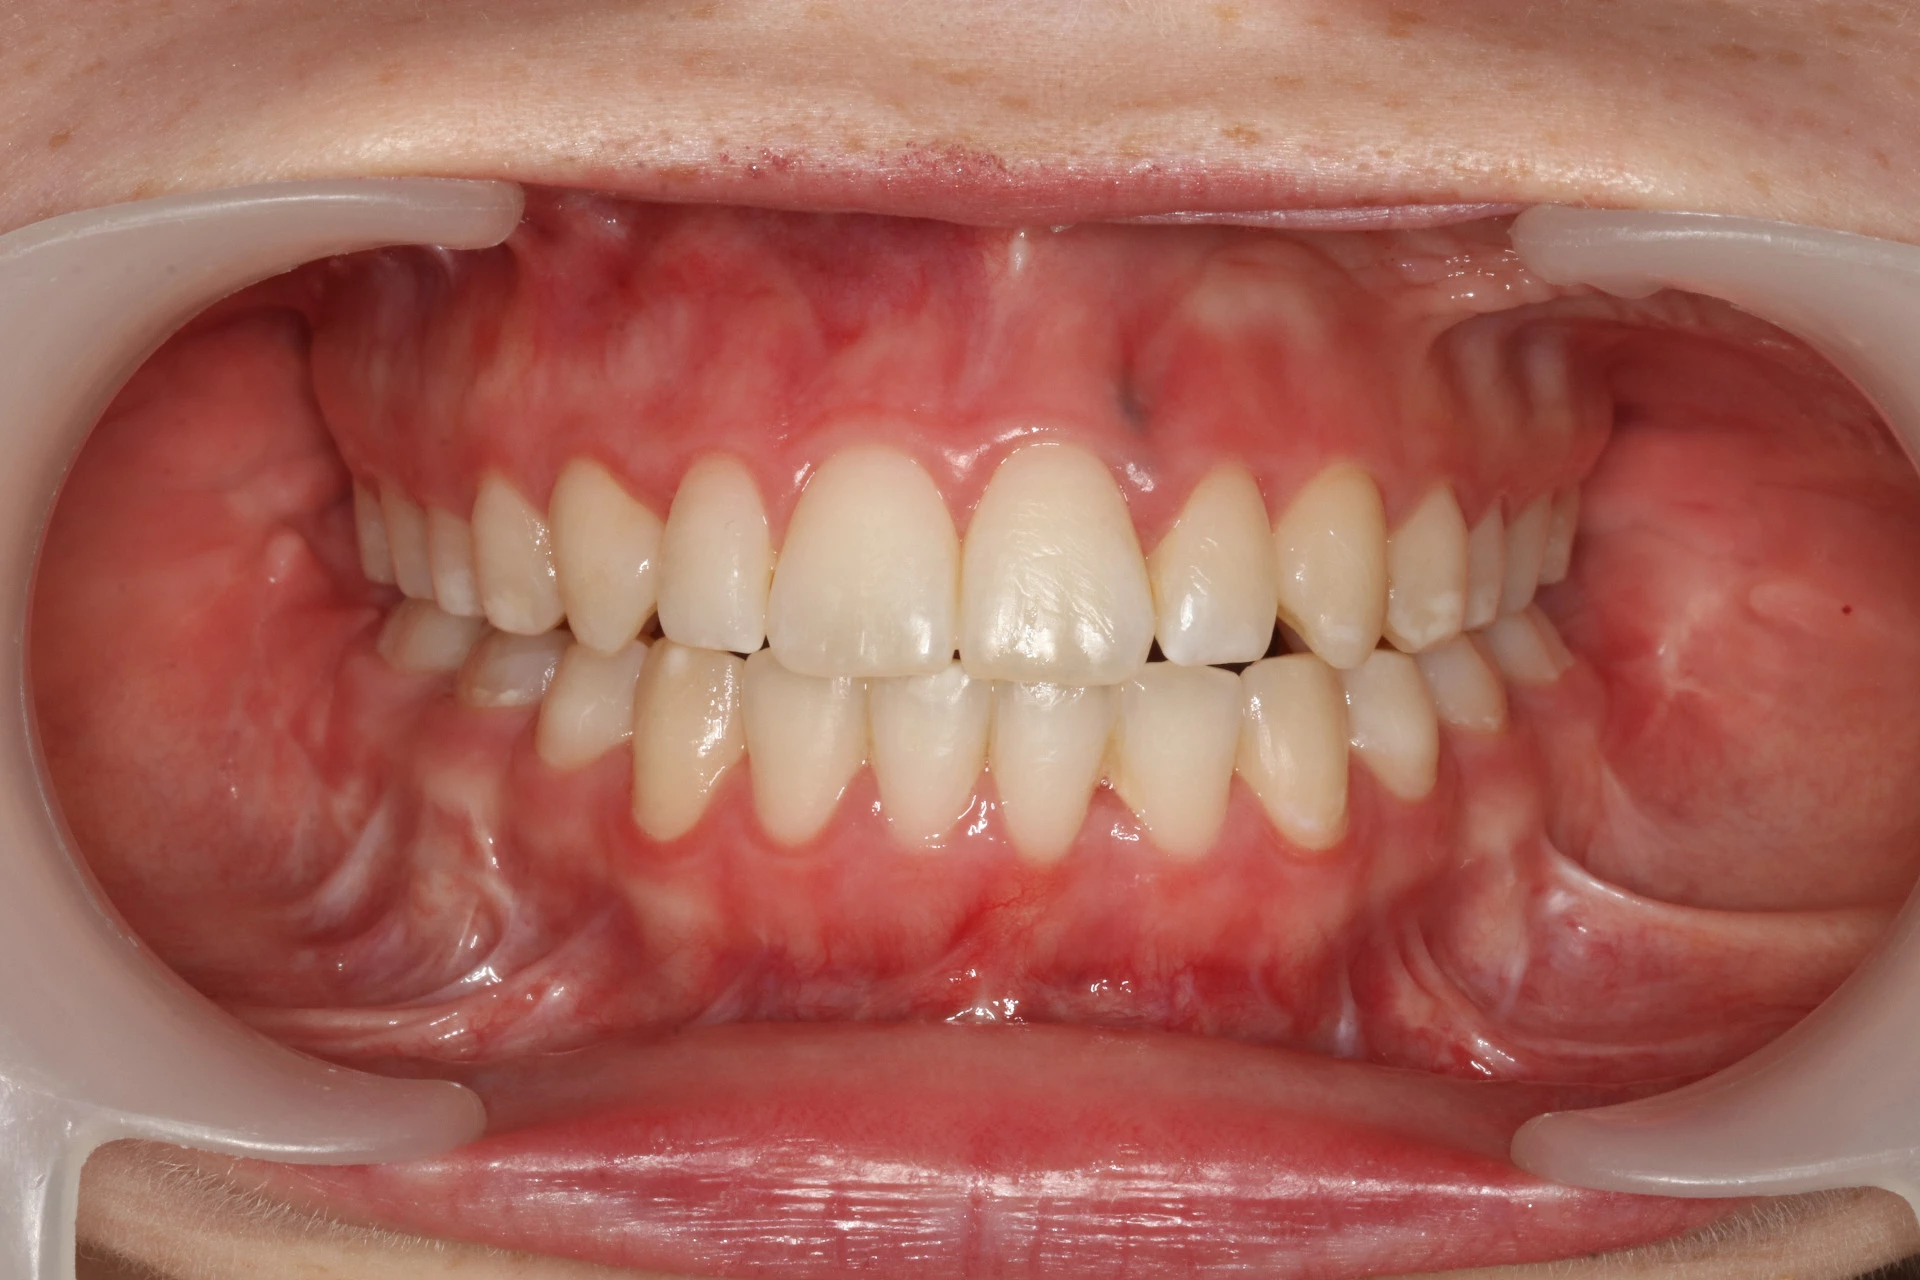

Vårt arbeid

Alle pasienter som vises har gitt skriftlig samtykke til at bildene kan brukes på klinikkens nettside.